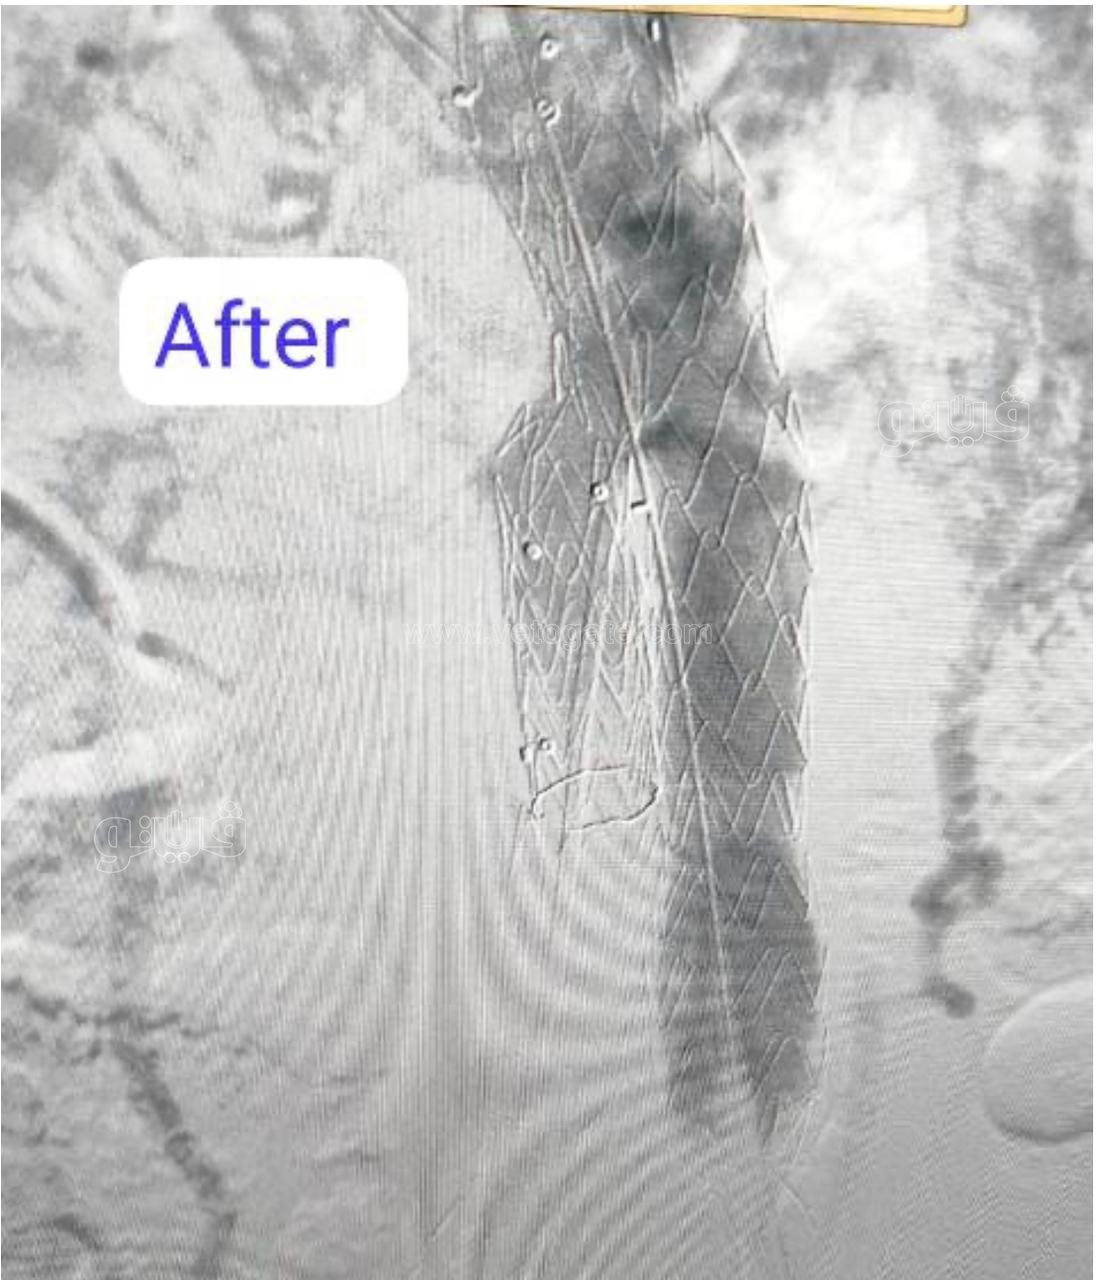

نجح فريق بقسم جراحة الأوعية الدموية بـ مستشفى بدر التابعة لكلية الطب بجامعة حلوان في إجراء تركيب قسطرة دقيقة جدًا لمريض يعاني من تمدد كبير في الشريان الأورطي والشريان الحرقفي الأيمن، حيث تم تثبيت دعامات مغطاة على هذين الشريانين لمنع انفجارهما، مما ساهم في إنقاذ حياته.

وأفاد الدكتور محمد فاضل، مدير مستشفى بدر أن الفريق الطبى الذى قام بإجراء القسطرة التشخيصية ضم كلًا من: " أحمد المهدى رئيس قسم جراحة الأوعية الدموية، شريف عمر كرداوى أستاذ جراحة الأوعية الدموية، أحمد عبد العليم مدرس جراحة الأوعية الدموية، حسام إبراهيم مدرس مساعد جراحة الأوعية الدموية، عمرو حسان مدرس مساعد جراحة الأوعية الدموية، أيمن مرسى، محمد مجدى، محمود أمير، مصطفى علاء، ومحمود العدل".